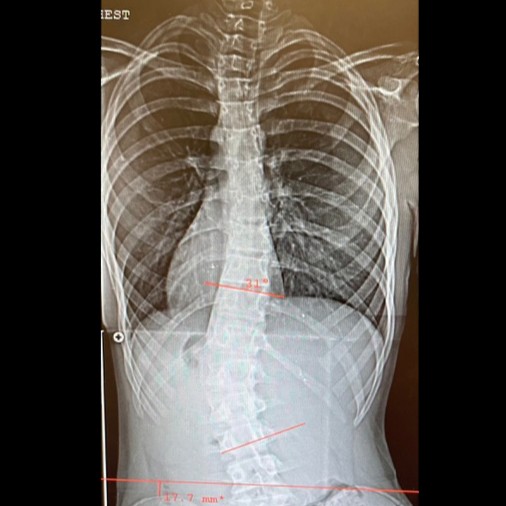

After an orthotist visit, I was fitted with my first brace. Choosing to keep my circumstance private to the outside world was an easy feat, since school and the world around me were shuttered due to the pandemic. I wore this painful brace for a year and grew another 5 inches. As I began leaning more to the right, my pediatrician suggested a podiatrist visit for a shoe lift. My mom had been worried that we weren’t getting the full picture and reached out to Children’s Hospital of Orange County to secure an orthopedist appointment. Within the month, we drove the +2 hours south where a nurse greeted me for a chest x-ray. The image appeared on a monitor that my parents and I stared at as we waited for the doctor. We finally had an answer as the doctor explained that my spine rotated forward and formed an S-shaped curve that would need to be braced due to adolescent idiopathic scoliosis. A TLSO Boston brace was made, to be worn 16 hours/day, that was restrictive, hot, and painful. I couldn’t figure out how to tolerably wear the brace at high school and wasn’t comfortable sharing my situation with anyone outside my family. So, all times outside of school, I wore this new brace for 1.5 years until I was 6’6” tall and well into 11th grade. With my extensive growth, the brace became ill fitting just around the time a family friend happened to mention Dr. Peter Newton at Rady Children’s Hospital. The summer prior to my senior year, I met Dr. Newton who began tracking my AIS. As my growth has slowed down, the risk of curvature lessened and I no longer wear a brace. It now sits in my closet as a reminder of a private journey.